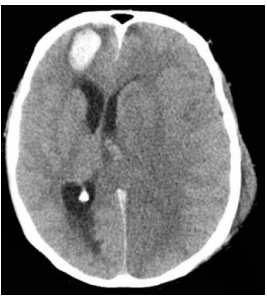

Analise a tomografia de crânio a seguir.

A partir da análise da imagem acima, é correto afirmar que o escore de Marshall vale: